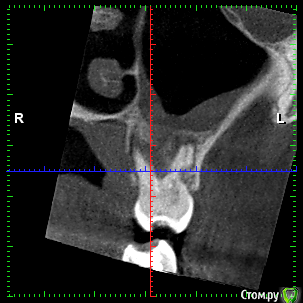

rezo47 Опубликовано 24 сентября, 2015 Автор Поделиться Опубликовано 24 сентября, 2015 Только пришло КТ, вопросов стало больше((( Ссылка на комментарий

kriokov Опубликовано 24 сентября, 2015 Поделиться Опубликовано 24 сентября, 2015 27 удаляйте Ссылка на комментарий

rezo47 Опубликовано 24 сентября, 2015 Автор Поделиться Опубликовано 24 сентября, 2015 (изменено) 27 удаляйтеДиагноз? Изменено 24 сентября, 2015 пользователем rezo47 Ссылка на комментарий

kladoffka Опубликовано 24 сентября, 2015 Поделиться Опубликовано 24 сентября, 2015 Хр пр 2 Ссылка на комментарий

kriokov Опубликовано 24 сентября, 2015 Поделиться Опубликовано 24 сентября, 2015 Диагноз?что хотите, на выбор(например- "не жилец" ) Ссылка на комментарий

red_butler Опубликовано 24 сентября, 2015 Поделиться Опубликовано 24 сентября, 2015 сначала гистология, потом лечение Ссылка на комментарий